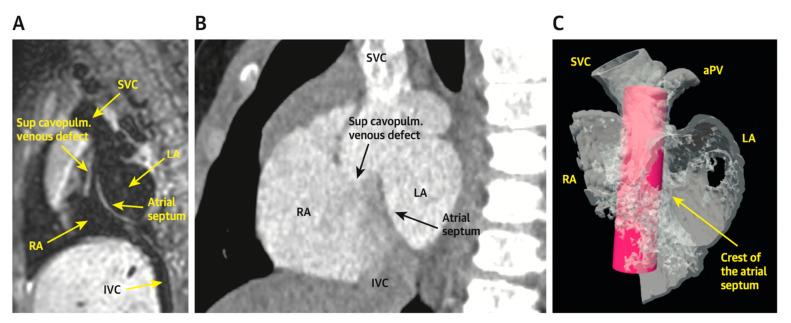

Management of congenital heart disease (CHD) has recently increased utilization of cross-sectional imaging to plan percutaneous interventions. Cardiac computed tomography (CT) and cardiac magnetic resonance (CMR) imaging have become indispensable tools for pre-procedural planning prior to intervention in the pediatric cardiac catheterization lab. In this article, we review several common indications for referral and the impact of cross-sectional imaging on procedural planning, success, and patient surveillance.

先天性心脏病(CHD)的管理最近增加了对横断面成像的利用,以规划经皮介入治疗。心脏计算机断层扫描(CT)和心脏磁共振(CMR)成像已成为小儿心导管实验室介入治疗前程序规划中不可或缺的工具。在本文中,我们回顾了转诊的几个常见指征以及横断面成像对程序规划、成功率和患者监测的影响。

Transcatheter Correction of Superior Sinus Venosus Atrial Septal Defects as an Alternative to Surgical Treatment.

J Am Coll Cardiol. 2020 Mar 24;75(11):1266-1278. doi: 10.1016/j.jacc.2019.12.070.